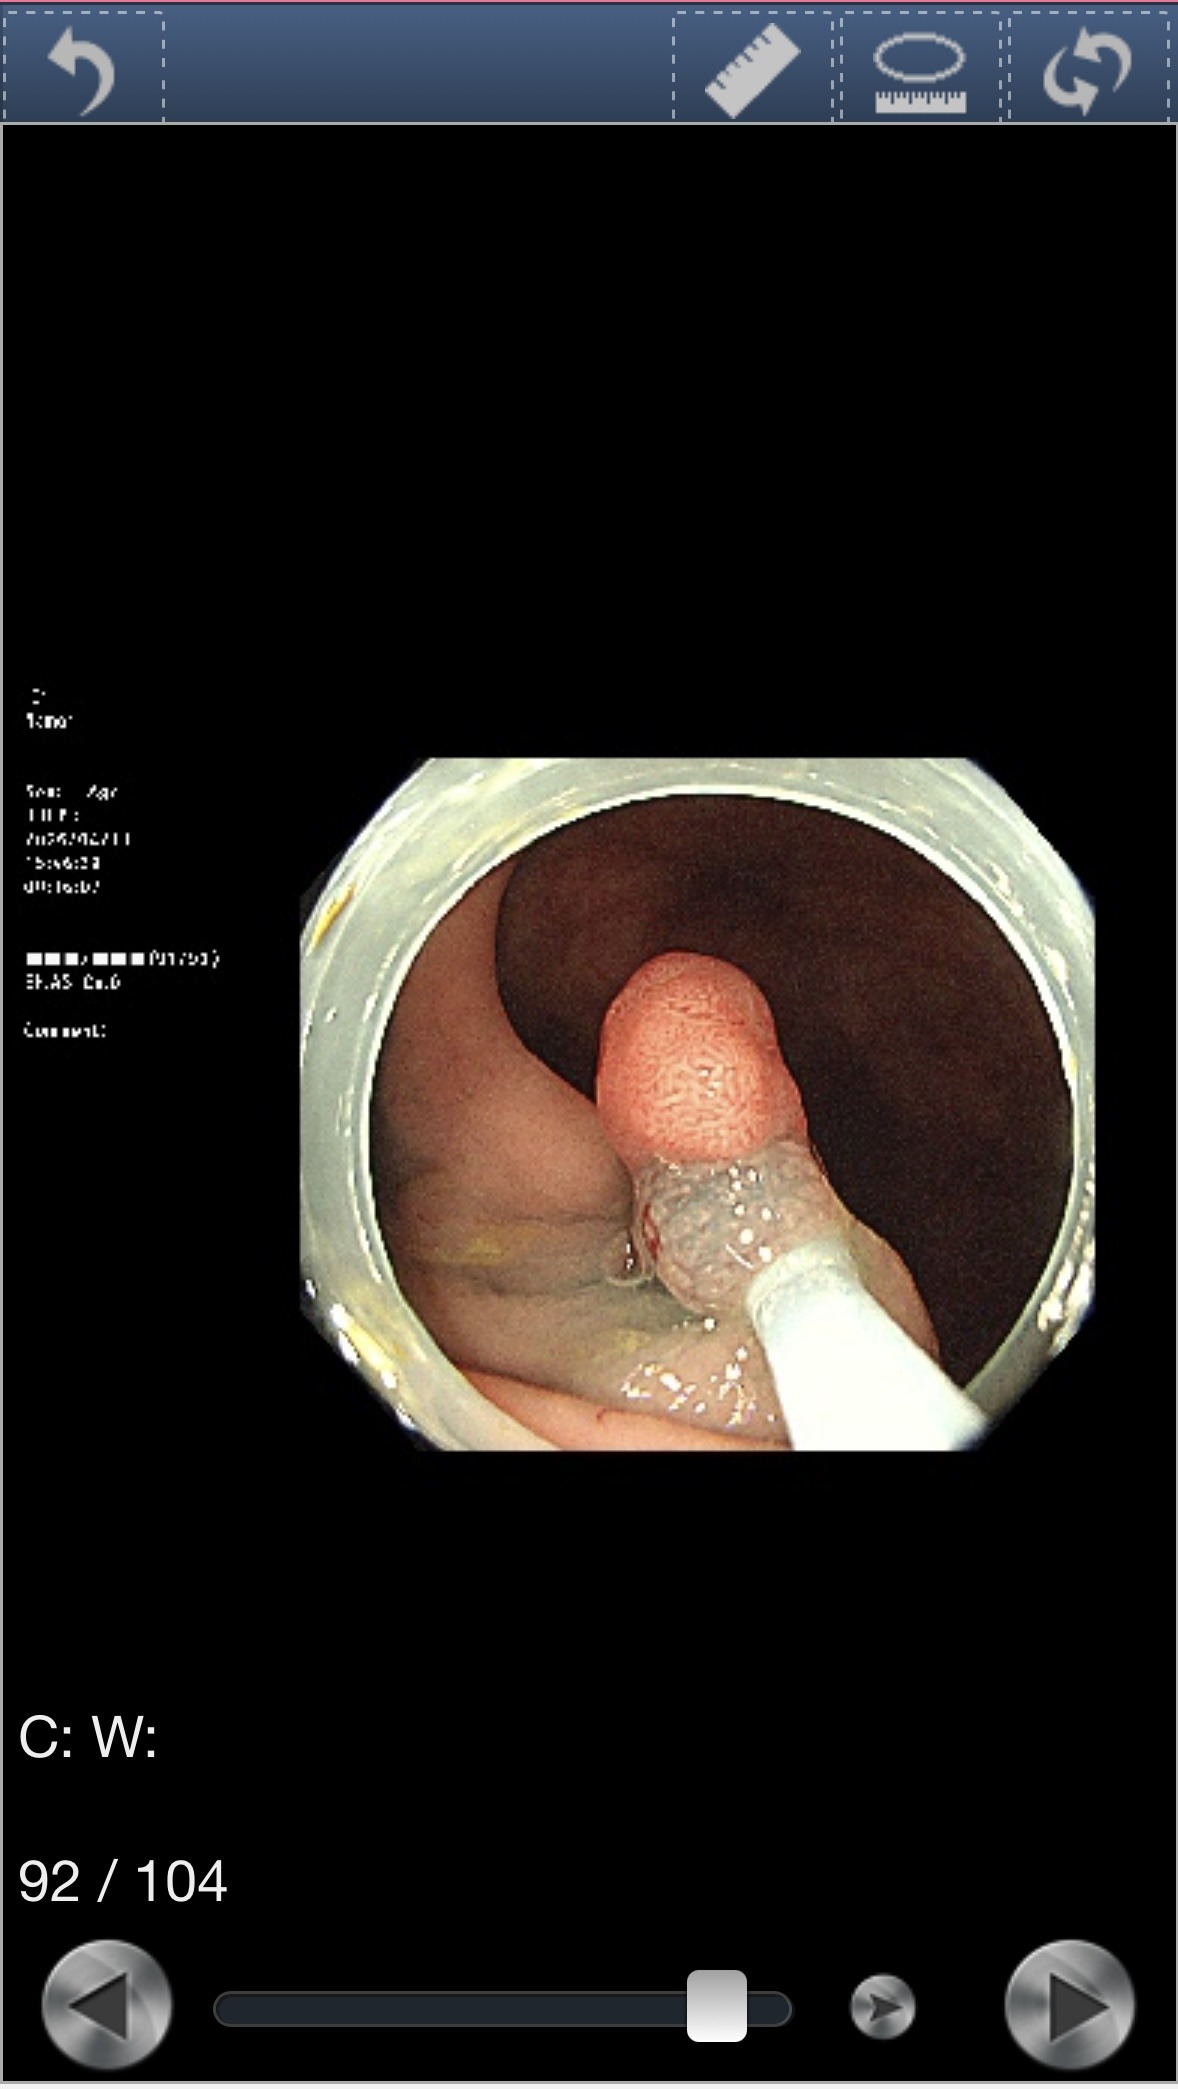

より精密に観察するため、色素を散布して輪郭を鮮明にした。

ドクターは「おそらく良性だと思います」と言ったが、念のため病理検査に出すため、その場で切除することになった。

切除後の粘膜はこうなる。

出血を防ぐため、切除した部分をクリップで留めた。このクリップは後日、自然と便と一緒に排泄される。

結果はまだ病理検査待ちだ。 ※結果が出次第、この記事に追記します。